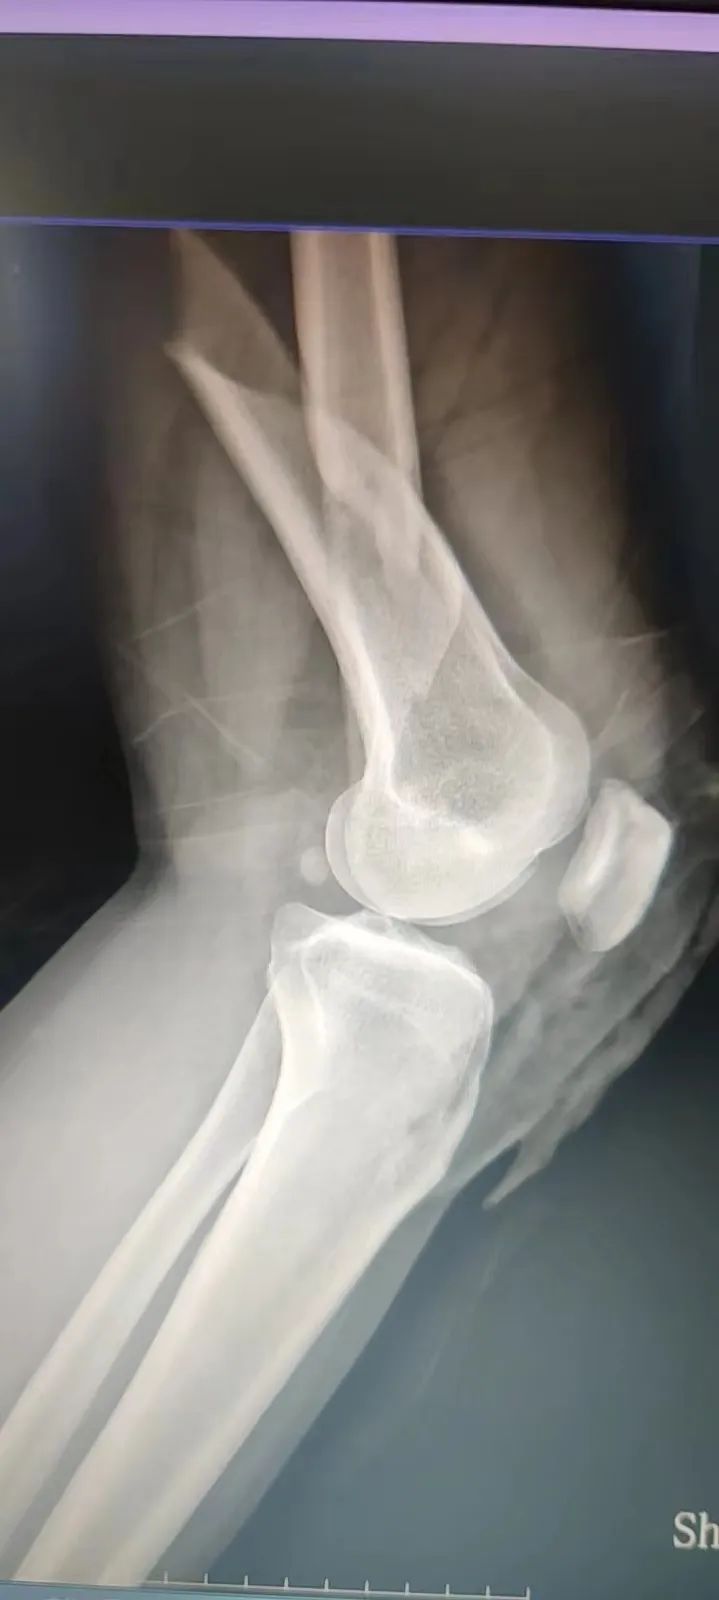

9月15日上午,在江桥医院住院部,医生在为刚做好手术的张女士复查。张女士告诉记者,9月14日上午她驾车时被后车追尾,导致身上3处骨折。“当时雨大风大,地上也很湿滑,后面的车没有及时刹车,就撞上了。”张女士说。

“雨天路滑,特别容易发生意外事故,像脱臼、骨折是比较常见的外伤。如果发生骨折,建议市民可先对骨折处进行临时固定,比如用木棍做成夹板,让骨折的肢体简易固定,防止二次损伤。”江桥医院骨科副主任医师刘颖赵说。

9月15日上午,在江桥医院住院部,医生在为刚做好手术的张女士复查。张女士告诉记者,昨天上午她驾车时被后车追尾,导致身上3处骨折。“当时雨大风大,地上也很湿滑,后面的车没有及时刹车,就撞上了。”张女士说。